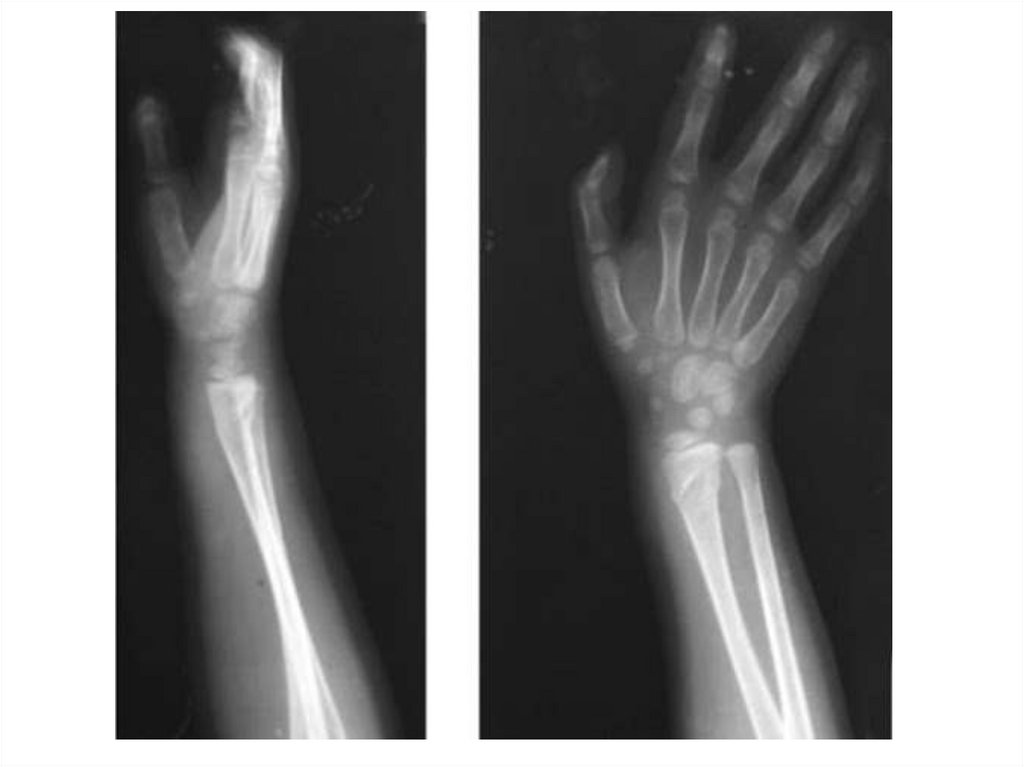

Назовите

• Вид исследования

• Область исследования

• Патологию